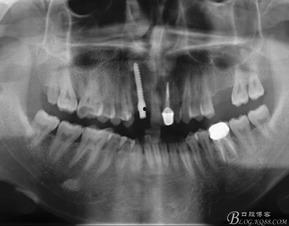

首先,得先弄清楚国产种植体是个啥。简单来说,种植体就是人工牙齿的“根”,它通过手术植入到牙槽骨中,然后与周围的骨头结合,成为支撑人工牙齿的基础。而国产种植体,就是我国自主研发和生产的一种种植体。

1. 手术过程:视频详细展示了种植体的手术过程,从术前准备到术后恢复,让观众对整个手术过程有了直观的了解。

2. 术后效果:视频中还展示了术后患者的恢复情况,让人看到了国产种植体的实际效果。

3. 专家解读:视频邀请了口腔专家对国产种植体进行了详细解读,包括种植体的种类、适用人群、注意事项等。